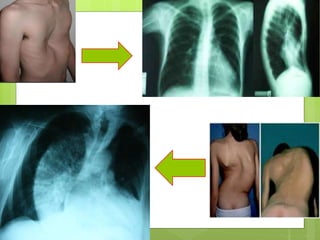

Hábito constitucional Brevilínio: HTA,DBT, DLP, hiperuricemia, Longilíneo: hipotensión arterial, TPSV, crisis de pánico y neurosis cardíaca. Marfán: aneurisma disecante de aorta.